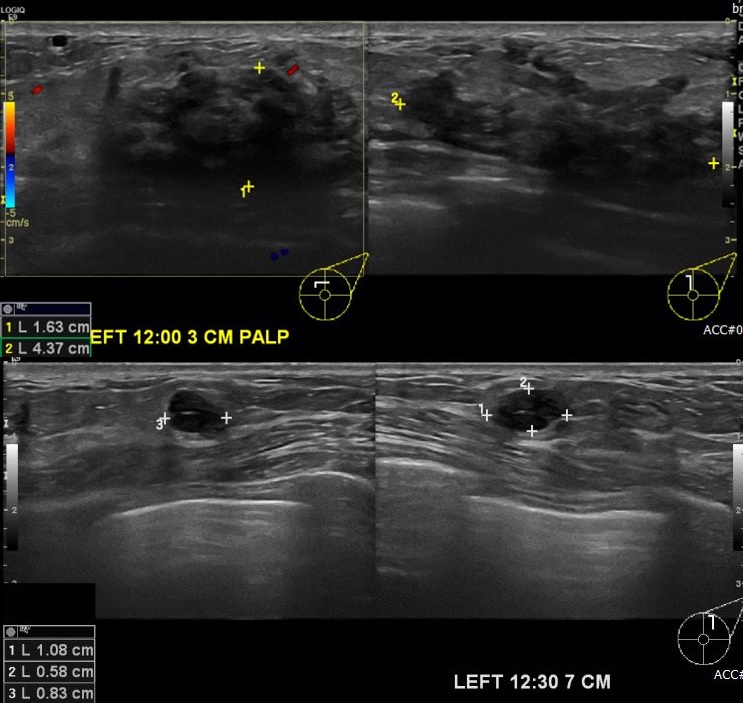

상기환자 좌측 만져지는 멍울로 내원하신 40대 여성분으로 좌측 12시 뱡향에서 3cm

떨어진 거리의 혹 과 12시 30분 방향에 7cm 떨어진 거리의 혹 각각 조직검사 시행하여

두곳 좌측 유관암 진단 되었습니다.